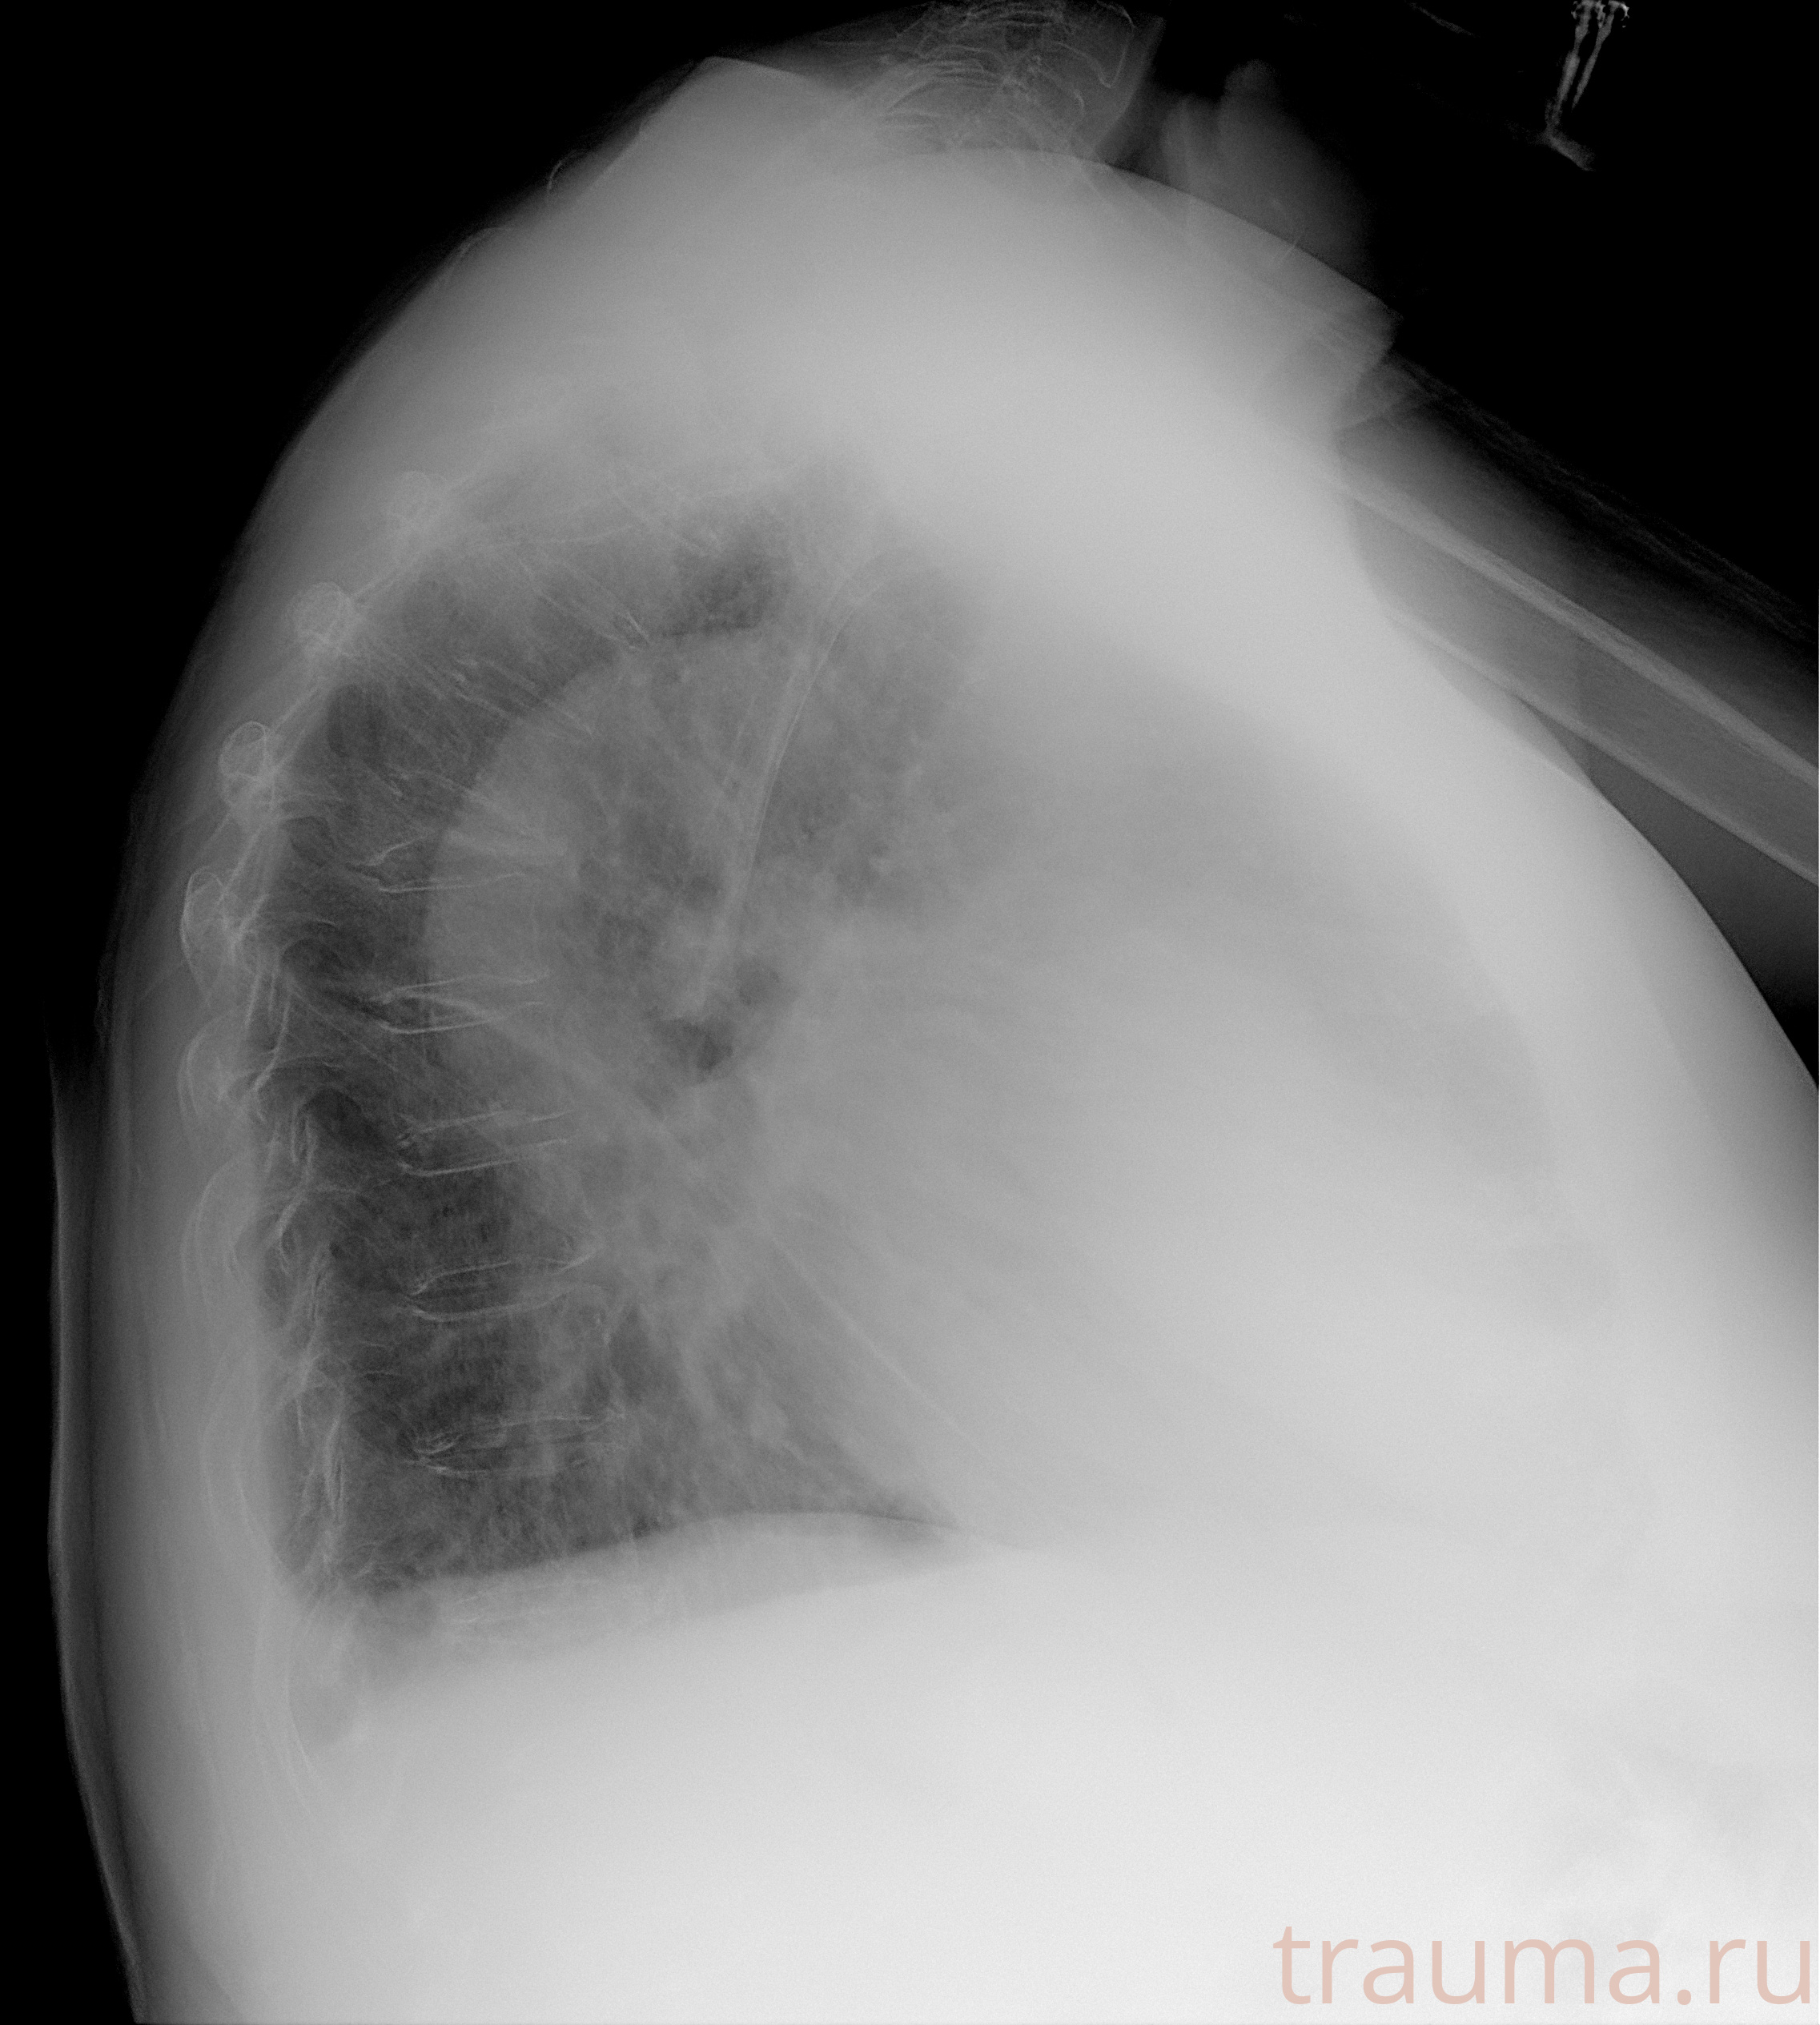

Рентген на дому: по вашему адресу приезжает врач-рентгенолог, травматолог-ортопед с мобильным рентгеновским аппаратом, проводит диагностику травмы или заболевания, делает необходимые рентгенограммы, дает рекомендации по дальнейшему лечению. Получить качественные снимки в домашних условиях возможно благодаря уникальной методике, разработанной МосРентген Центром для института  Склифосовского